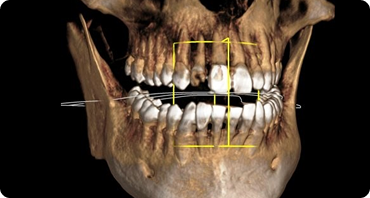

치료 전 3D 디지털 진단을 통한

수술 계획으로 예기치 않은

부작용을 줄일 수 있습니다.

저선량 3D CT

저선량 3D CT를 통한 환자의 잇몸뼈 상태,

신경위치를 데이터화하여 정밀한 계획을 수립합니다.